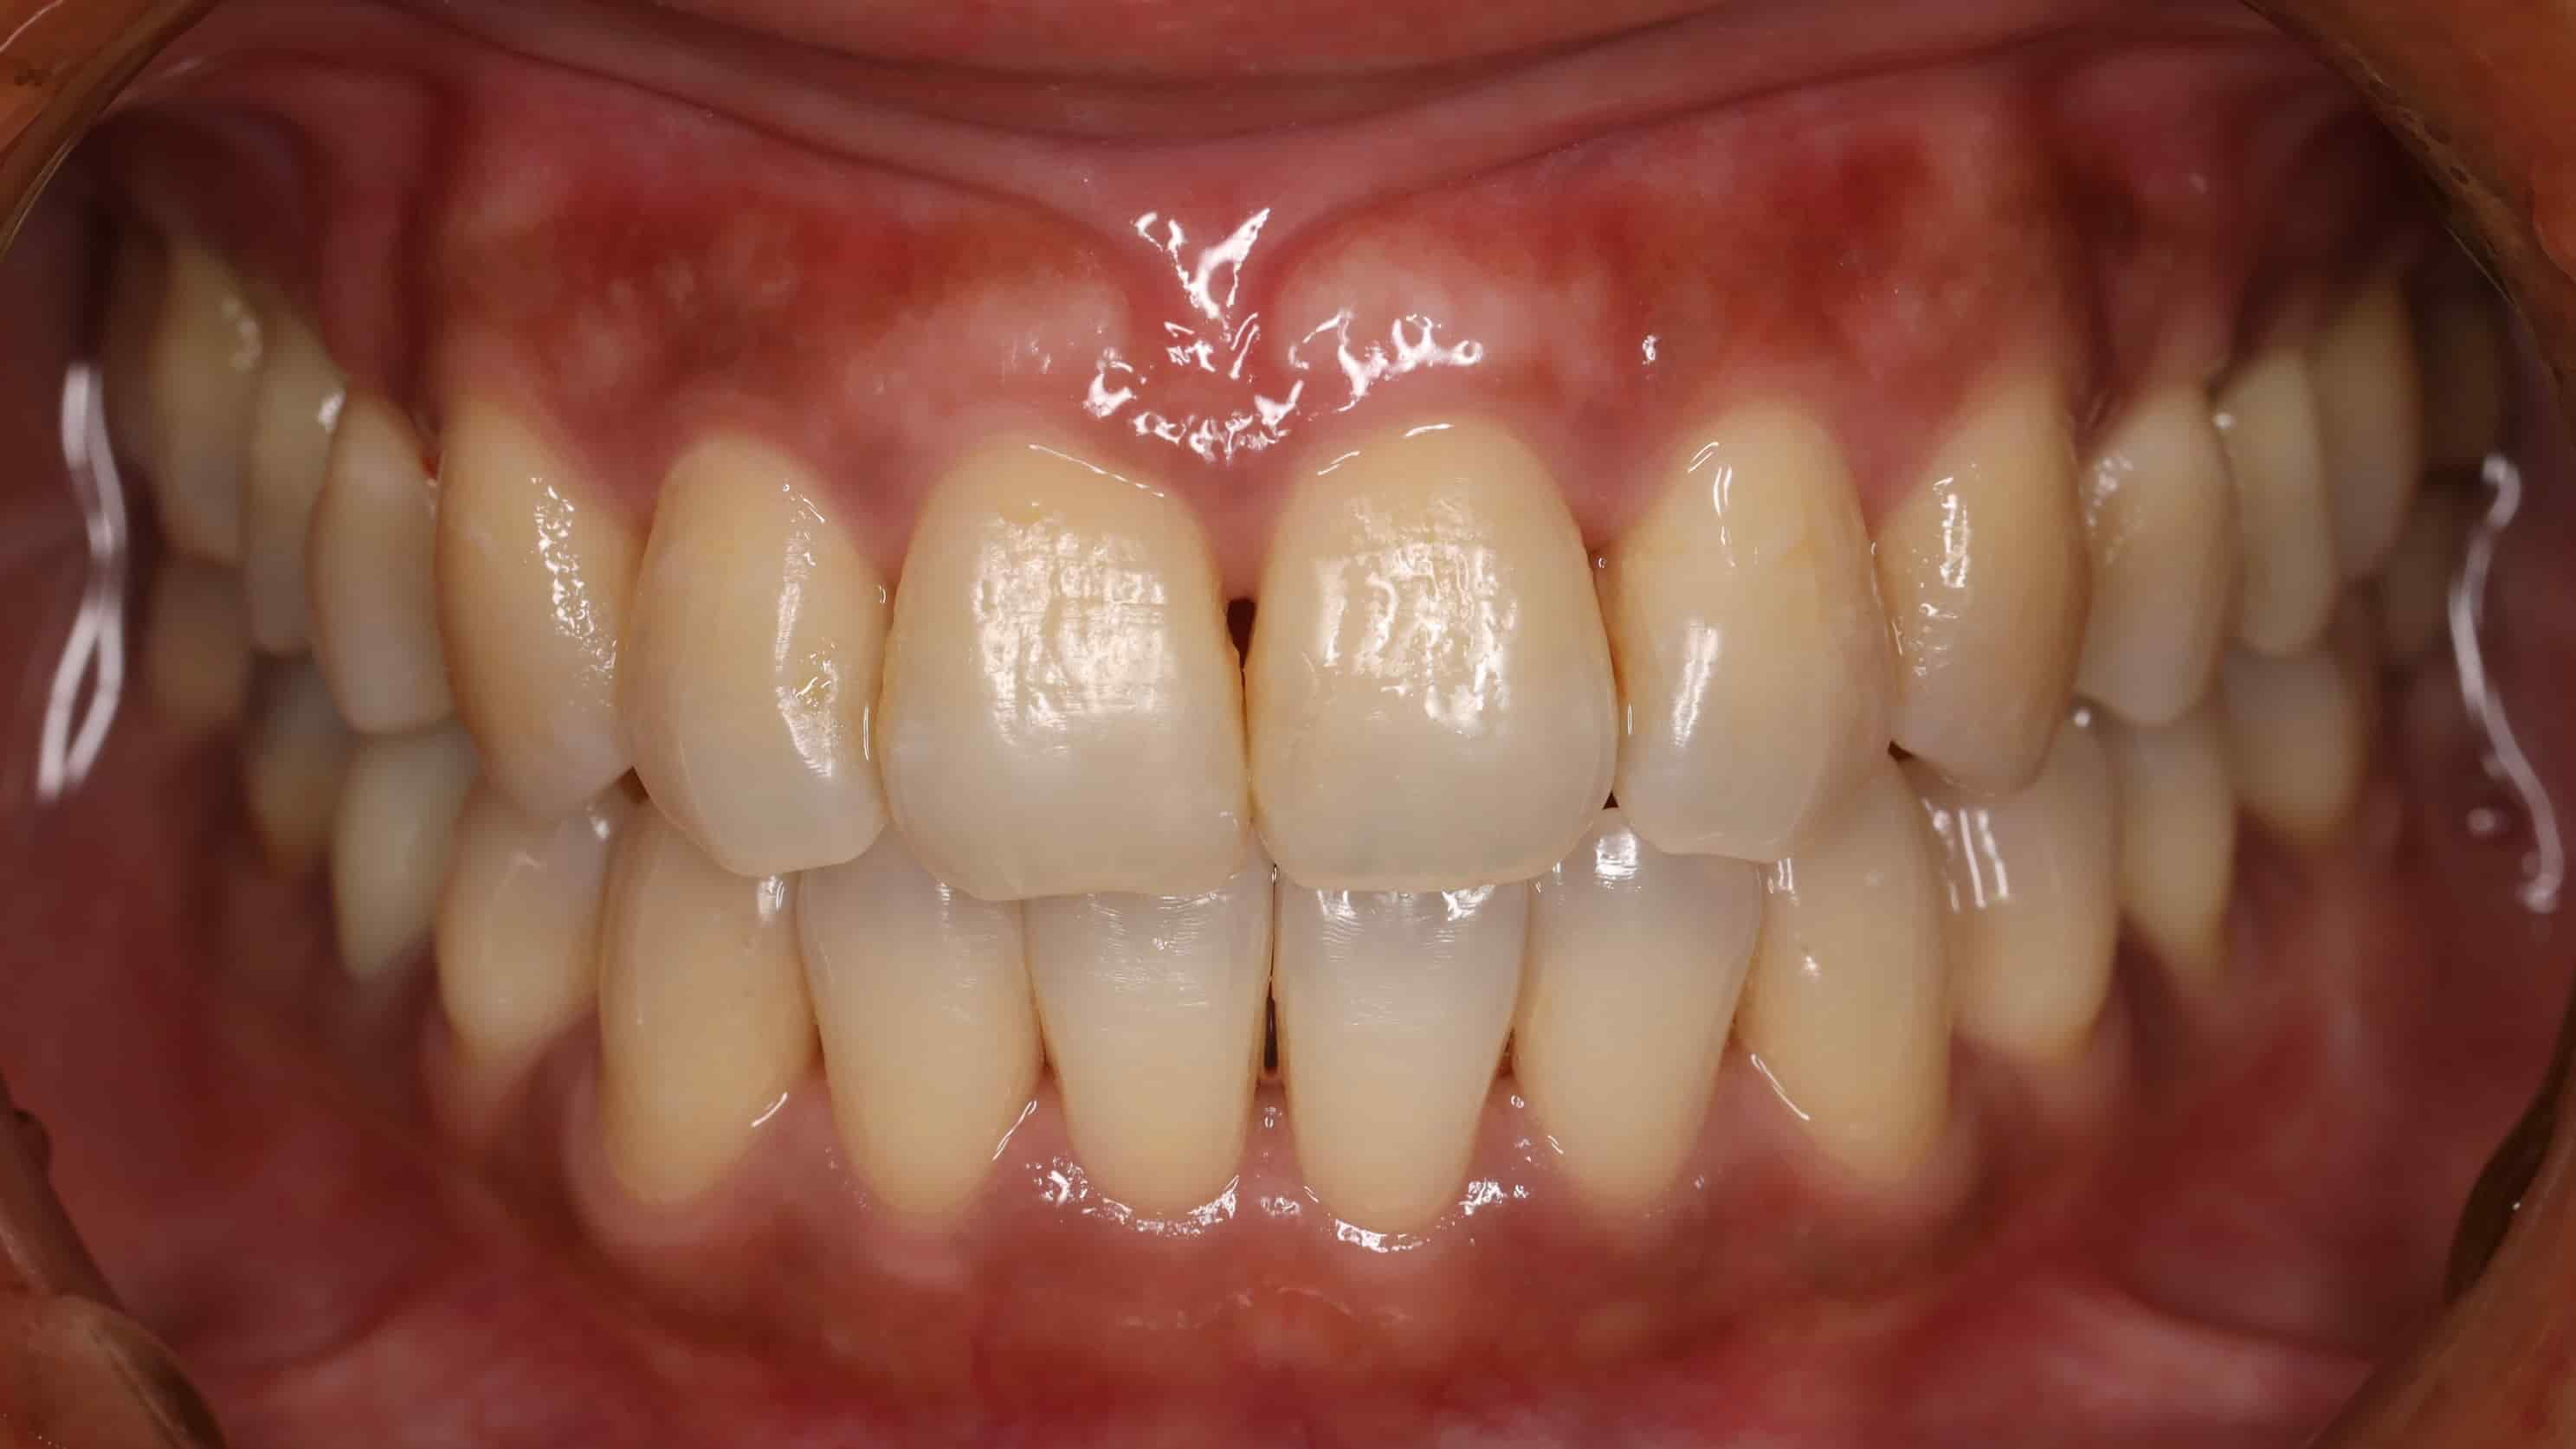

植牙完成後,繼續進行矯正治療做最後收尾,讓牙縫完全關閉,牙齒排列整齊,並把臨時假牙都更換程正式牙套,完成整個治療過程。整個治療過程中,最讓我們開心的是看到古小姐越來越有自信,當問題一個個被解決,古小姐的笑容也越來越燦爛,當治療結束時,她不只有了滿意的笑容,兩邊咬合也恢復正常,吃東西再也不會有壓力和疼痛了,口腔的美觀與健康都恢復,看到她那麼開心,我們也覺得所有的努力都值得了。